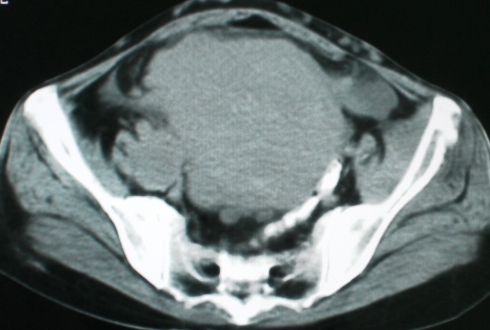

以下是引用zsl6918在2008-11-4 19:14:00的发言:[br]多发转移性改变,子宫改变不除外为原发灶